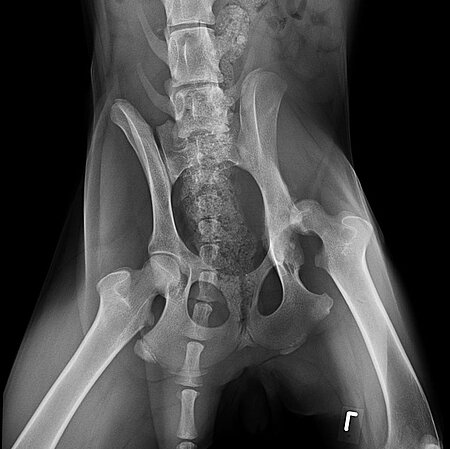

Umgehend wurde die Maus unserer Tierärztin vorgestellt, die die Hände über dem Kopf zusammenschlug. Schleunigst ging es zum Spezialisten, wo wir unseren Verdacht durch ein Röntgenbild bestätigt bekamen. Eine Femurkopfluxation, leider schon älter. Bei sofortiger Behandlung hätte man Alea gegebenenfalls sogar ohne große Operation schnell helfen können, aber jetzt, Monate später, kommen wir um diese nicht mehr herum. Knapp 800,-€ kostete die Operation, danach folgt die monatelange, kostenintensive Physiotherapie, um eine gute Genesung zu erzielen. Leider hat sich die langanhaltende Verletzung auch auf ihr Gangbild ausgewirkt, sodass sie lernen muss, wieder ordentlich zu laufen, damit sich auch die Muskulatur aufbauen kann.